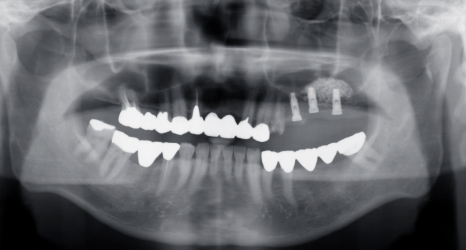

術後パノラマエックス線像です。骨造成がしっかりできているかはレントゲンの2次元の情報には限界があります。